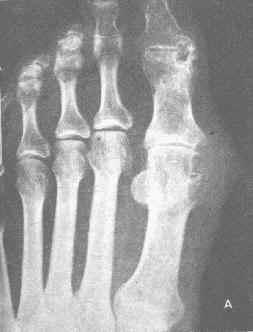

痛风